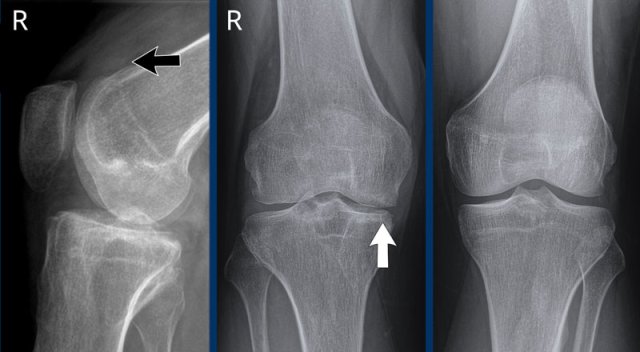

Hemophilic arthropathy of the right knee (Arnold-Hilgartner classification: Stage III) Hemophilic arthropathy of the right knee (Arnold-Hilgartner classification: Stage III)

This patient has a history of hemophilia and repetitive hemarthros.

Images

Distention of the suprapatellar recess of the right knee due to hemarthrosis (black arrow).

There is narrowing of the medial joint space caused by cartilage destruction and secondary osteoarthritis (white arrow).

Subchondral bone cyst formation underneath the intercondylar eminence.

No erosions.

The Arnold-Hilgartner classification is a plain radiograph grading system for haemophilic arthropathy of the knee.

This patient has a history of repetitive hemarthrosis caused by a vascular malformation (not visible on plain radiography).

The image of the right knee shows joint space narrowing, subchondral cysts formation and erosions of the medial and lateral tibial plateau.

Normal left knee joint for comparison.